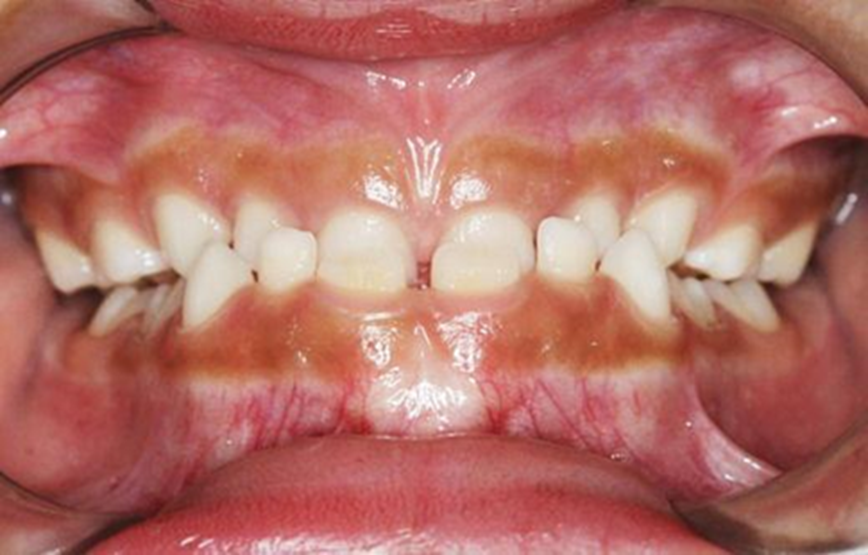

Figura 2. Foto intrabucal. Vista frontal.

Autor: María Gabriela Flores Bracho. Fuente: Historia Clínica de M. C. M. H. 6 años. 04-2010.

Figura 3. Fotos intrabucales. Vista lateral.